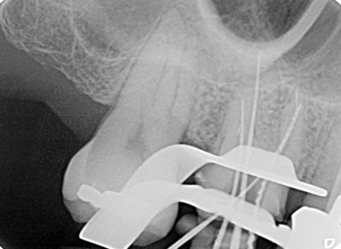

多根根管治療

治療前